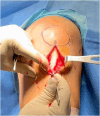

Graft-tunnel mismatch (GTM) is a known technical challenge that can occur with anterior cruciate ligament reconstruction when using a patellar tendon autograft. Two-incision anterior cruciate ligament reconstruction is a well-established technique with excellent outcomes and can serve as an excellent tool to prevent GTM. Traditionally, 2-incision femoral tunnel drilling has been performed using an over-the-top guide through a lateral incision, but more modern retrograde reamer guides can allow this to be done percutaneously. We detail how a minimally invasive 2-incision femoral tunnel drilling technique can be used in patients with patellar tendon lengths that are longer than average to avoid GTM.